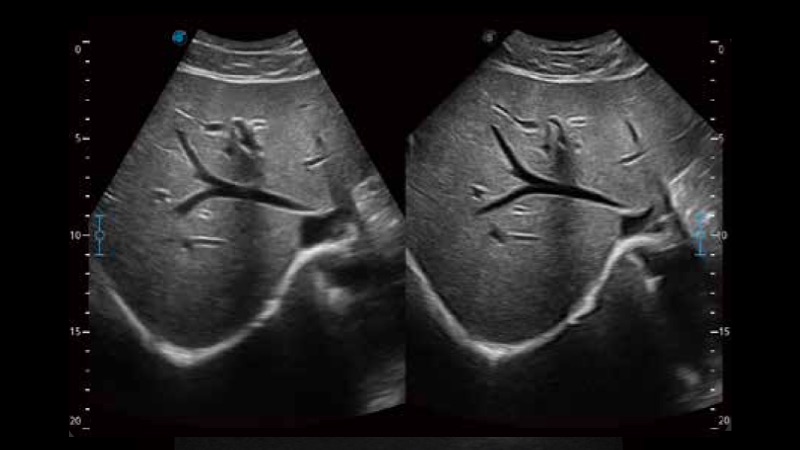

凭借狗万官方网站先进的成像技术和优异的探头技术提供的清晰的图像表现,您可以更自信地做出临床决策。

单晶体凸阵探头